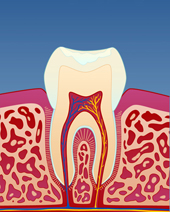

Om man over lengre tid har vært plaget med tanngnissing, vil man kunne se dette på tennene. Disse blir slitt og får rette kanter. Man kan også slite seg gjennom det ytterste laget på tannen (emaljen) slik at tannbenet (dentinet) blir synlig. Dette kan føre til at tennene blir mer ømfintlige og følsomme i det daglige.

figur I